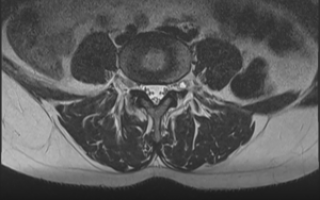

- Изолированное магнитно-резонансное исследование. Метод определяет степень компрессии нервных корешков, обнаружить шванномы различного калибра, включая мелкие множественные очаги.

Дополнительно проводится магнитно-резонансная томография спины во всех отделах позвоночника, узи очага поражения. Невринома требует дифференциальной диагностики от прочих экстрамедуллярных опухолей, воспалительной или компрессионно-ишемической невропатии.

Лечение шванномы позвоночника начинается с магнитно-резонансной томографии. Если диагноз оставляет сомнения, то назначают уточняющие исследования.